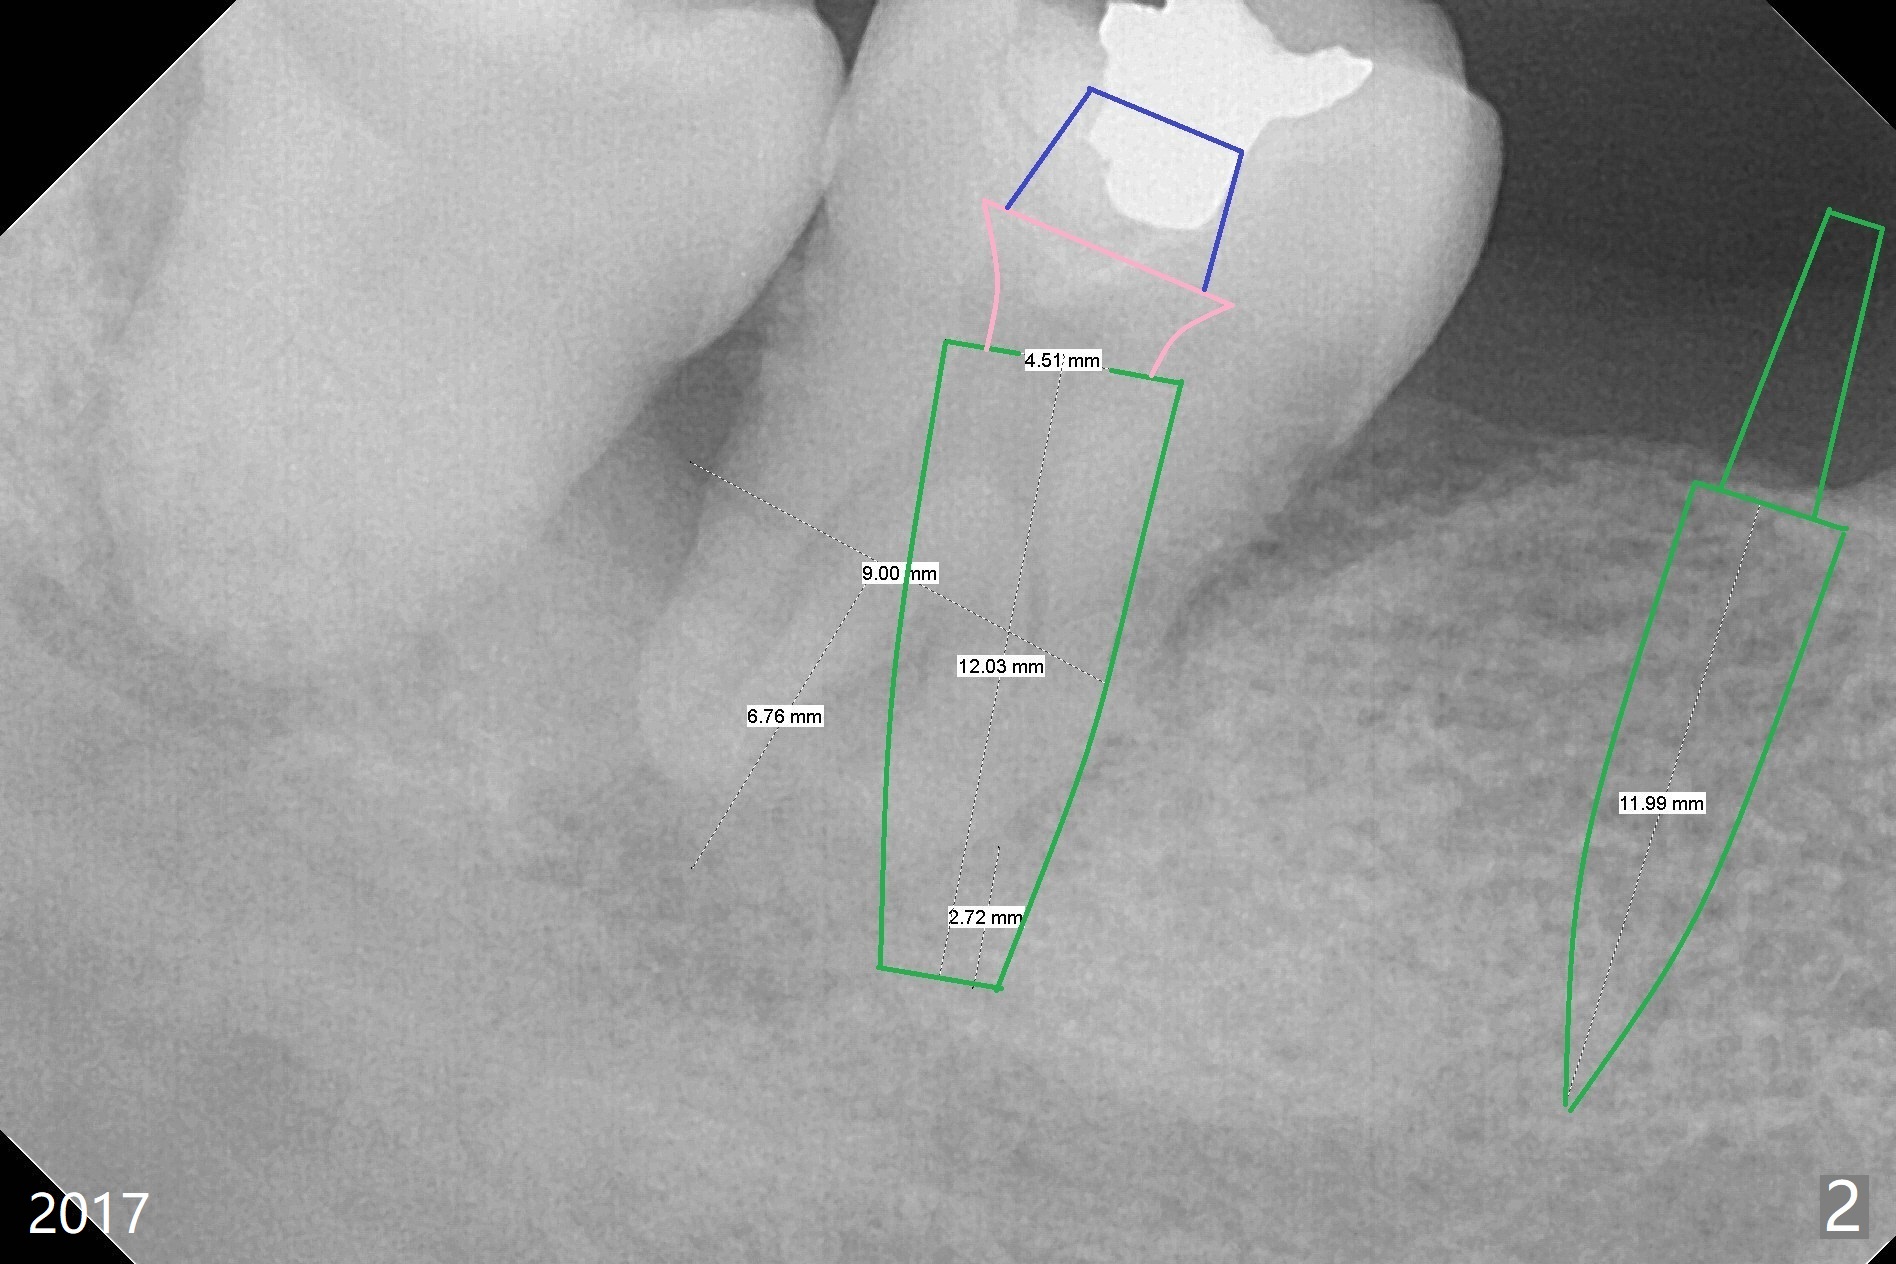

A 49-year-old man requests implants because of difficulty in eating. The teeth #19 and 30 are missing, while #18 and 31 have mobility. For the sake of dental insurance, an implant will be placed at #30 first. Due to long standing edentulism with opposing supraeruption (Fig.1 arrow), the ridge must be narrow. After ridge reduction, the bone height will be ~ 10 mm (Fig.2). To prevent screw loosening, a 1-piece implant will be used. To compensate for height limitation, the diameter of the implant will be 3.5 or 4.0 mm. If the restorative height is favorable, fabricate a provisional prior to suturing so that subgingival margin is possible (to improve cosmetics and prevention of food impaction). If the vertical height is limited for provisional, create clearance barely enough for periodontal dressing. Overprep of abutment height in the early stage may be related to easy dislodgement of the crown later on.